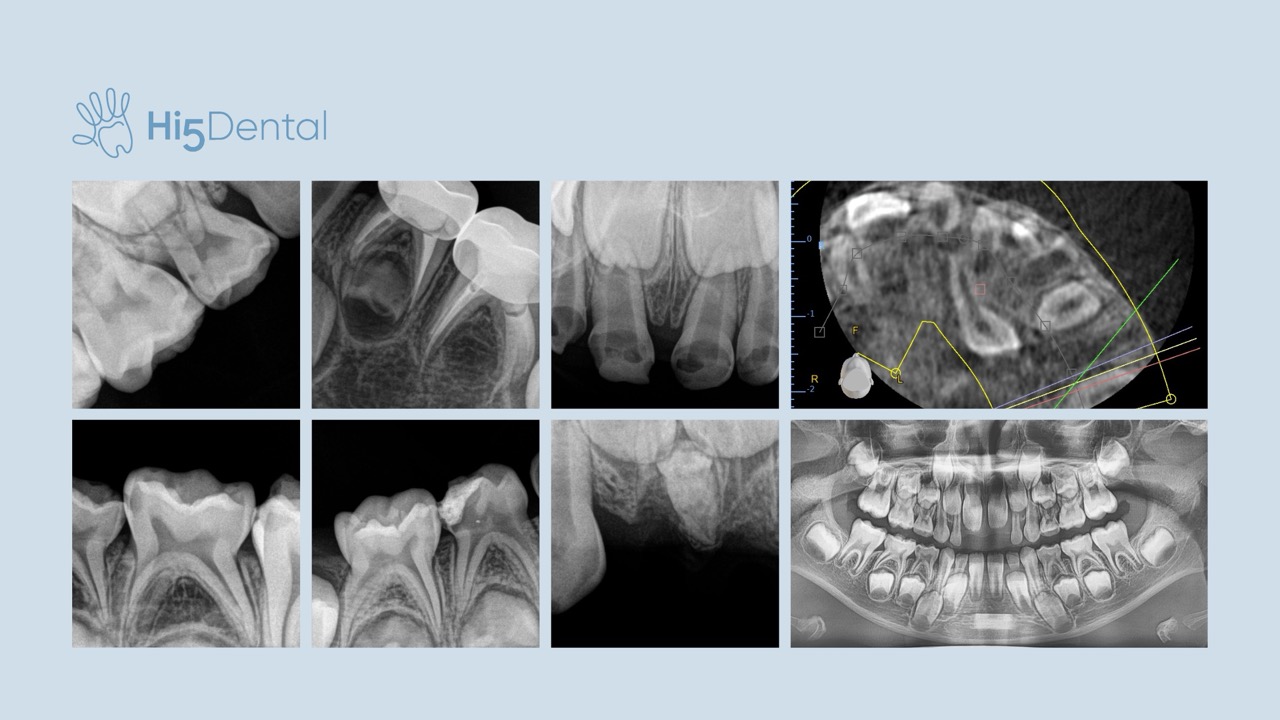

Rentgen zębów mlecznych u dzieci – kiedy i po co się go wykonuje?

RTG stomatologiczne u dzieci to bezpieczne i szybkie badanie, które pozwala stomatologowi zobaczyć więcej niż w zwykłym badaniu wzrokowym. Dzięki nowoczesnym aparatom cyfrowym możliwe jest wczesne wykrycie próchnicy, ocena rozwoju zębów sta...